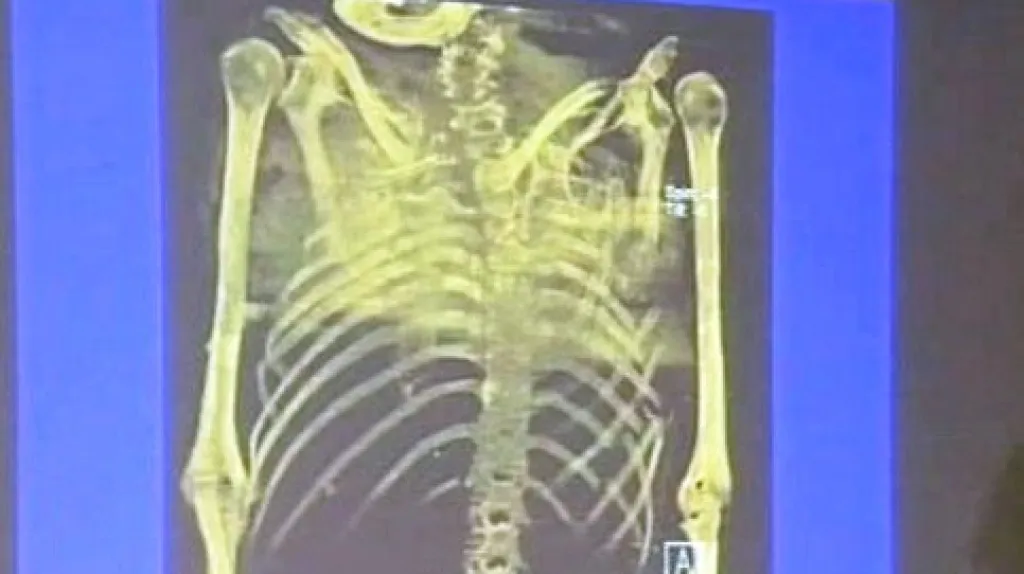

Spor o příčiny smrti polského exilového premiéra po dlouhá desetiletí rozdělovala politiky, historiky i veřejnost. Soudní znalci teď věří, že už pravdu znají. Podle zprávy a důkazů, které zveřejnil polský Úřad národní paměti v Krakově, generál nebyl uškrcen, zastřelen či jinak zavražděn. Jeho smrt způsobila mnohačetná zranění po pádu letadla nad Gibraltarem. Sikorski měl polámaná žebra, končetiny, těžký úraz hlavy a další úrazy.

„Ke smrti došlo v důsledku zranění mnoha orgánů po velmi silném úderu. Není pochyb o tom, že jde o zranění typická pro letecké katastrofy,“ potvrdil lékař Tomasz Konopka.